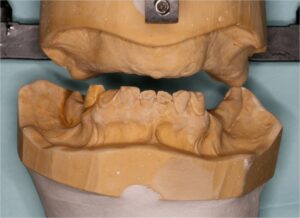

- Κινητη προσθετικη, δηλαδη μερικες και ολικες οδοντοστοιχιες